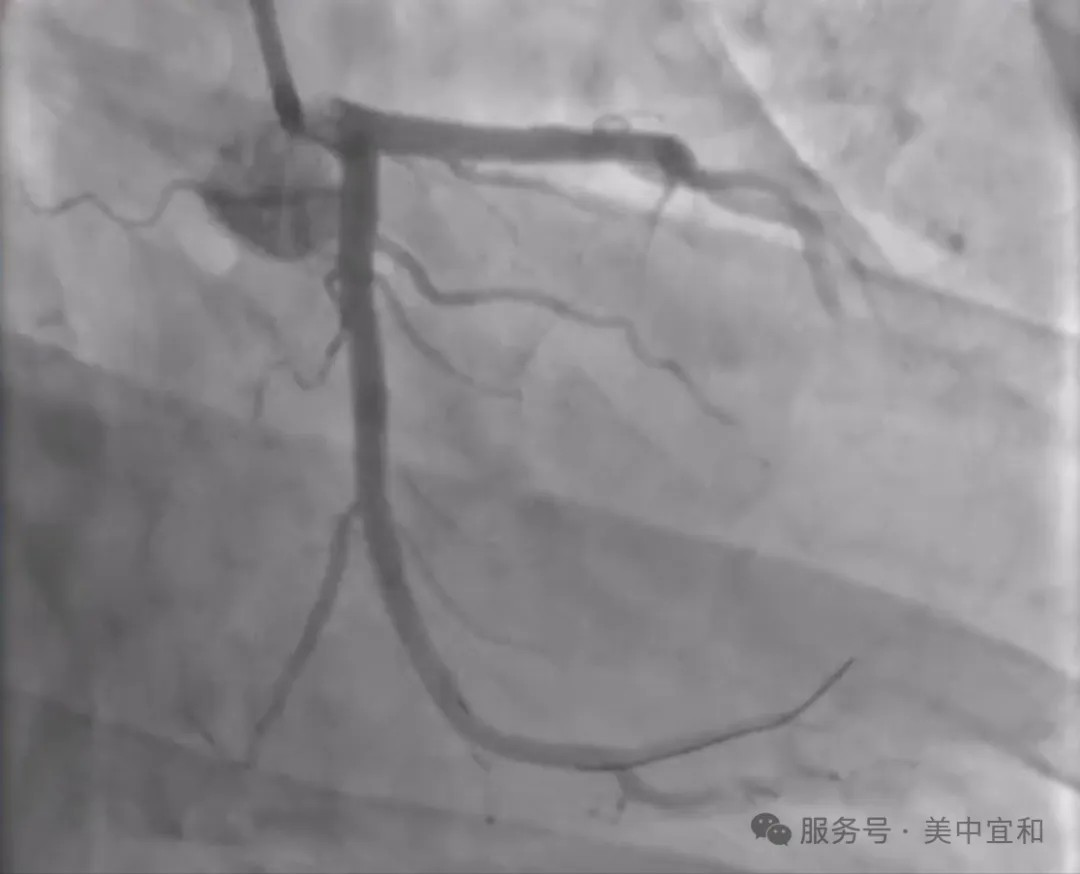

冠脉造影下汪先生的血管影像比想象中还要“糟糕”:左冠回旋支(LCX)中段长段高度狭窄,最重处达 90%,属于高危复杂病变。长段狭窄意味着需要精准覆盖病变全程,且容易出现支架贴壁不良、血管夹层等风险;90% 的重度狭窄则要求手术过程中对血流的保护极为严格,稍有不慎就可能引发心肌缺血甚至梗死。

(冠脉造影可见汪先生回旋支中段约90%重度狭窄)